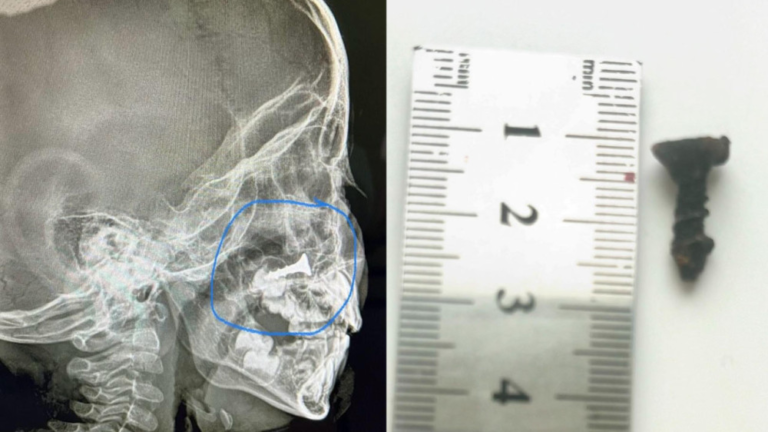

Шокирующая история: Ребенок полгода жил с шурупом в носу на юге Казахстана